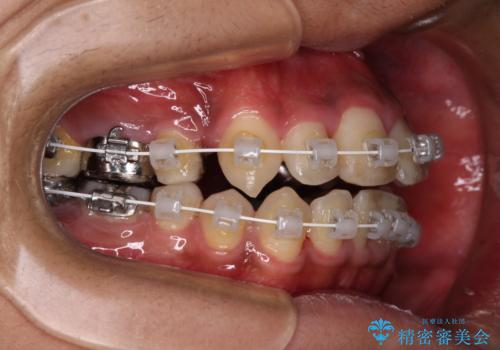

- 審美装置

自己管理が煩わしいとのことで、表側のワイヤー装置にて治療を進めて行くこととしました。

舌の突出癖により開咬となっていたため、突出癖改善のためのトレーニングをしっかりと行っていただき、予定の期間で無事に治療を終えることができました。